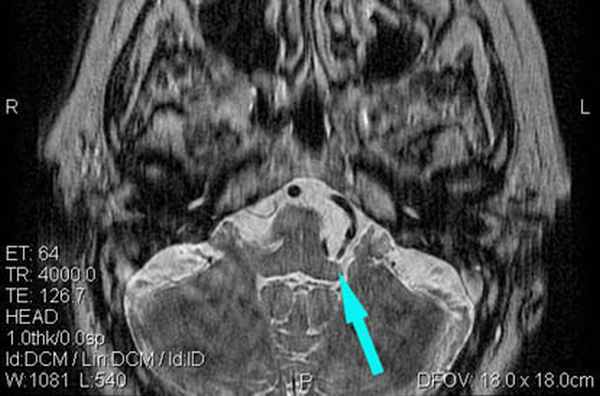

(Справа) При аксиальной МРТ Т2 ВИ у пациента с гемифациальным спазмом определяется долихоэктазия позвоночной артерии, воздействующей на зону выхода корешка лицевого нерва во внутренних отделах цистерны ММУ. Приблизительно у 50% пациентов с гемифациальным спазмом обнаруживаются изменения на МРТ, обычно на тонкосрезовых Т2 последовательностях или МРА.

Визуализируется близкое расположение артериального сосуда и лицевого нерва (указано стрелкой), что может являться причиной гемифациального спазма